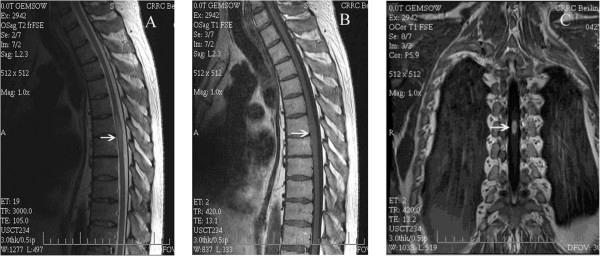

A 42-year-old man developed paraplegia after an open cholecystectomy under epidural anesthesia. Spinal cord infarction, acute transverse myelitis, and intramedullary neoplasms were ruled out by histopathologic examination, and intramedullary spinal tuberculoma at the T6-T7 level was identified. Despite surgical treatment and subsequent antituberculous therapy, the patient retained some disability attributable to the delay in diagnosis.

Physicians should be aware of coexisting disease as a cause of paraplegia following procedures using epidural anesthesia. Magnetic resonance imaging is the most sensitive diagnostic test, although it is still difficult to differentiate spinal cord infarction, myelitis, intramedullary spinal tuberculoma, and neoplasms from imaging features alone.

一名42岁男性在硬膜外麻醉下行开腹胆囊切除术后发生截瘫。组织病理学检查排除了脊髓梗死、急性横贯性脊髓炎和脊髓内肿瘤,确诊为T6 - T7水平的脊髓内结核瘤。尽管进行了手术治疗及后续抗结核治疗,但由于诊断延误,患者仍遗留部分残疾。

医生应意识到并存疾病可能是硬膜外麻醉手术后截瘫的原因。磁共振成像(MRI)是最敏感的诊断检查,不过仅从影像学特征仍难以区分脊髓梗死、脊髓炎、脊髓内结核瘤和肿瘤。